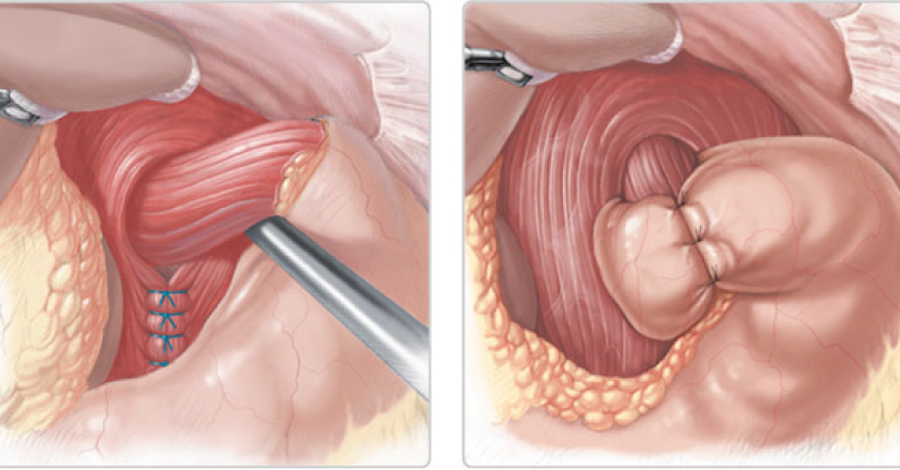

Umbilical

Epigástrica

• Umbilical

• Epigástrica